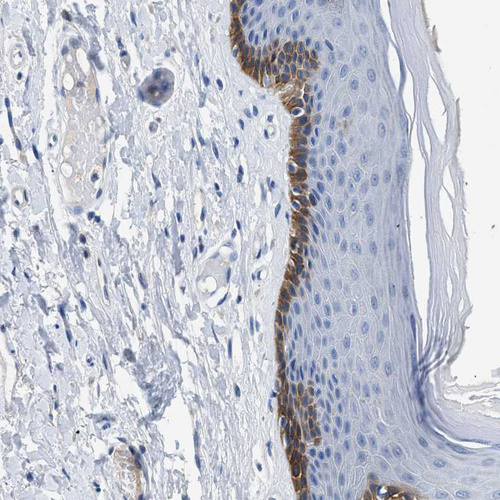

Immunohistochemistry analysis in human skin and lymph node tissues using HPA016662 antibody. Corresponding SLC10A6 RNA-seq data are presented for the same tissues.